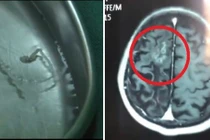

| Đau đầu do u não gây tăng áp lực nội sọ nên ở giai đoạn đầu cơn đau thường âm ỉ và kéo dài. Giai đoạn sau cùng với chứng đau đầu có kèm theo buồn nôn, giảm thị lực hoặc các dấu hiệu của thần kinh khu trú ví dụ như liệt chi thể, liệt dây thần kinh sọ não, và mắt mờ. Lúc này người bệnh cảm thấy đau đầu liên tục và uống thuốc có dấu hiệu không giảm. Ảnh minh họa: Internet |

Đau đầu do u não: Đau đầu do u não gây tăng áp lực nội sọ nên ở giai đoạn đầu cơn đau thường âm ỉ và kéo dài. Giai đoạn sau cùng với chứng đau đầu có kèm theo buồn nôn, giảm thị lực hoặc các dấu hiệu của thần kinh khu trú ví dụ như liệt chi thể, liệt dây thần kinh sọ não, và mắt mờ. Lúc này người bệnh cảm thấy đau đầu liên tục và uống thuốc có dấu hiệu không giảm.